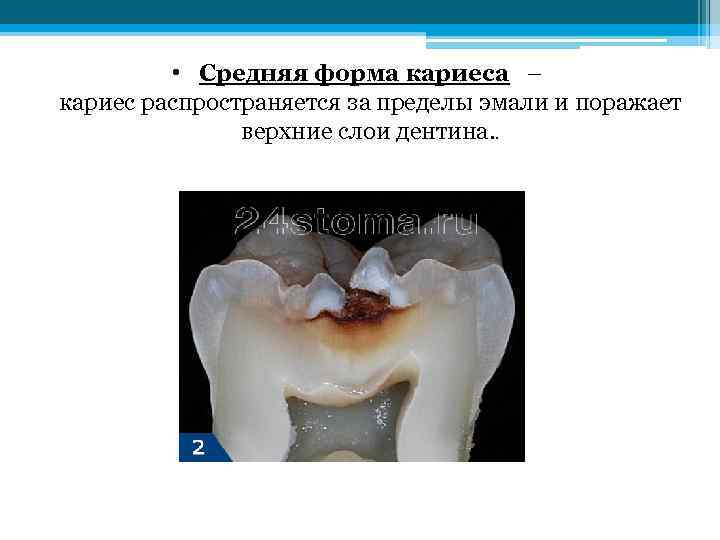

• Средняя форма кариеса – кариес распространяется за пределы эмали и поражает верхние слои дентина. .

• Средняя форма кариеса – кариес распространяется за пределы эмали и поражает верхние слои дентина. .